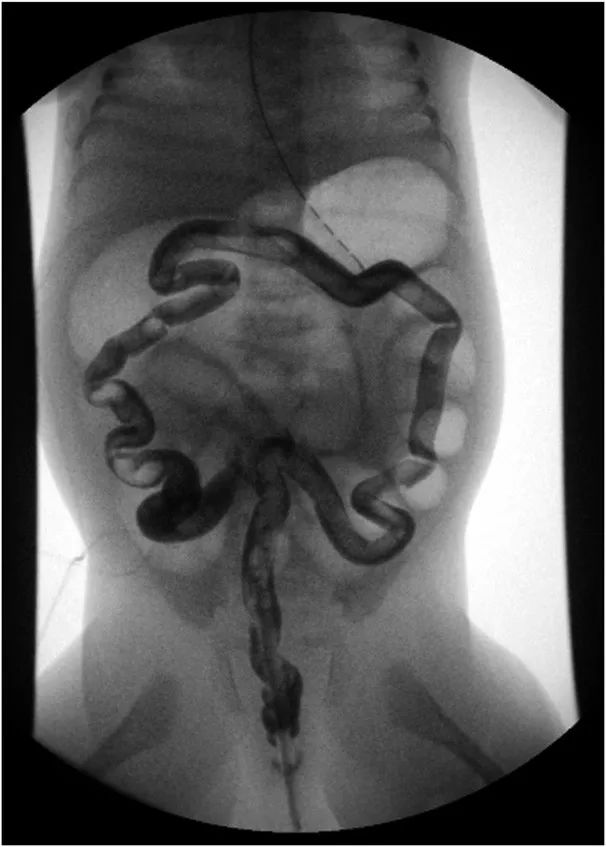

考虑到婴儿患有先天性巨结肠疾病,胎粪延迟排出超过24小时,以及远端肠梗阻的腹部影像学改变,进行了灌肠对比剂造影检查(图2)。

根据上图(图2),影像学诊断是什么?

先天性细小结肠症

(congenital microcolon)

又称胎儿结肠,是新生儿肠梗阻所引起的继发征象。因结肠细小幼稚,管径<1.0 cm而得名,由一组先天性消化道畸形引起,常见于肠闭锁、胎粪性畅梗阻和全结肠型无神经节细胞症,属于一种少见的新生儿先天性肠道畸形。